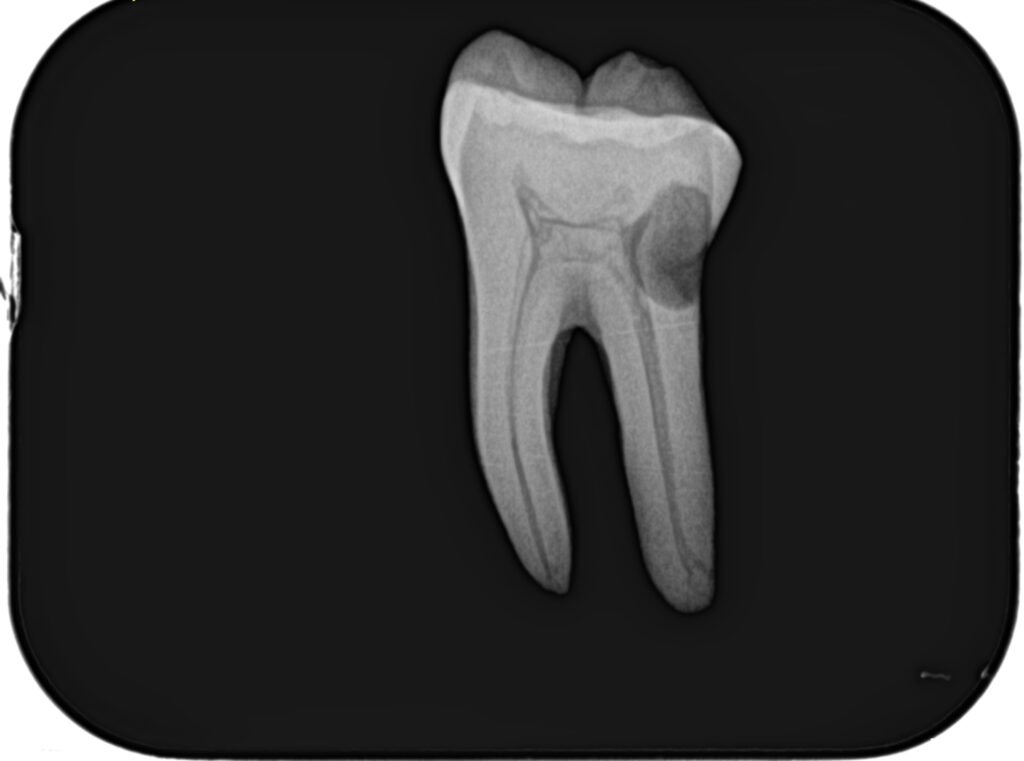

根管形成が終了すれば、根管充填だ。

その際に必要な物品は以下である。

日曜日は実習を行った。

土曜日の内容を投影した実習であった。

2本の歯牙で実習し、あっという間に1日は終了した。